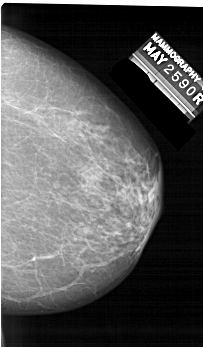

A_1423_1.RIGHT_CC

RIGHT_MLO LINES 6136 PIXELS_PER_LINE 3346 BITS_PER_PIXEL 12 RESOLUTION 43.5 NON_OVERLAY